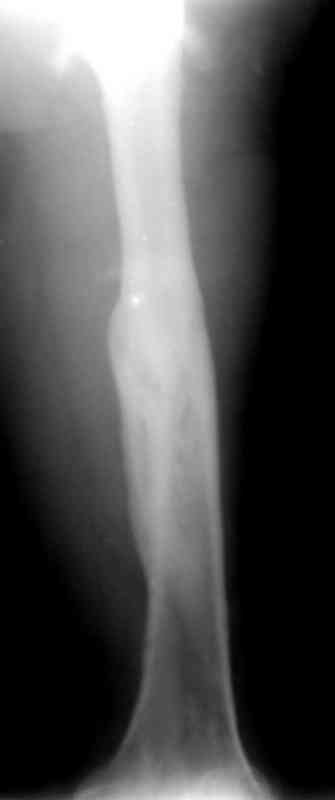

месяцев дистракции укорочение левого бедра удалось полностью устранить. 22.02.00, т.е. через 2 месяца после повторного остеосинтеза, больному произведено дистальное блокирование штифта двумя винтами и демонтирован аппарат Илизарова. В течение 2 недель после операции больной ходил с помощью костылей, потом 2 недели с тростью. Опороспособность и функция оперированной конечности полностью восстановились через 4 недели после операции.

Фиксаторы удалены через 12 месяцев после операции, выполненной по поводу замедленной консолидации перелома бедра с его укорочением.

На финальных снимках видно - сращение прям таки железное. Если Вы не устали отвечать, осмелюсь задать еще вопрос - что-то принимал пациент в целях ускорения сроста (кальций, режим питания). Интересны также вопросы восстановления функций конечности - в какой период были рекомендованы группы упражнений для восстановления основных групп мышц?